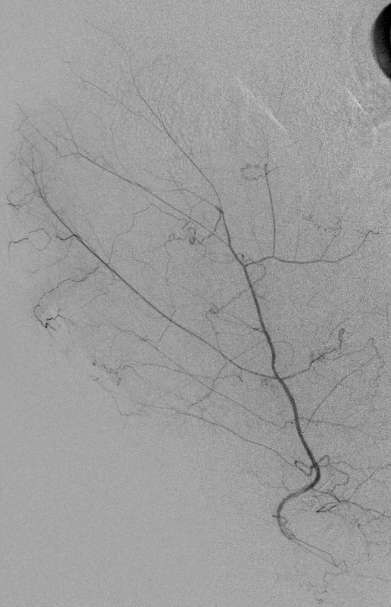

病例2:终末肾患者,肝硬化腹水。腹水穿刺引流后低血压,CT扫描发现活动性出血,造影剂外溢

术后